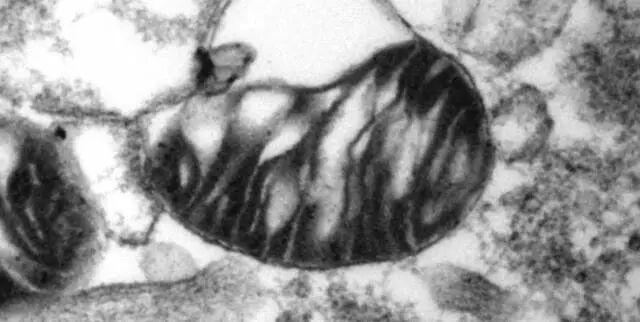

国际生殖医学界认为,卵子的质量与卵母细胞内的线粒体可能存在着必然相关。线粒体负责生产人类生命活动必需的几乎所有能量,素有人体“能量工厂”之称。

▲高倍电子显微镜下的线粒体